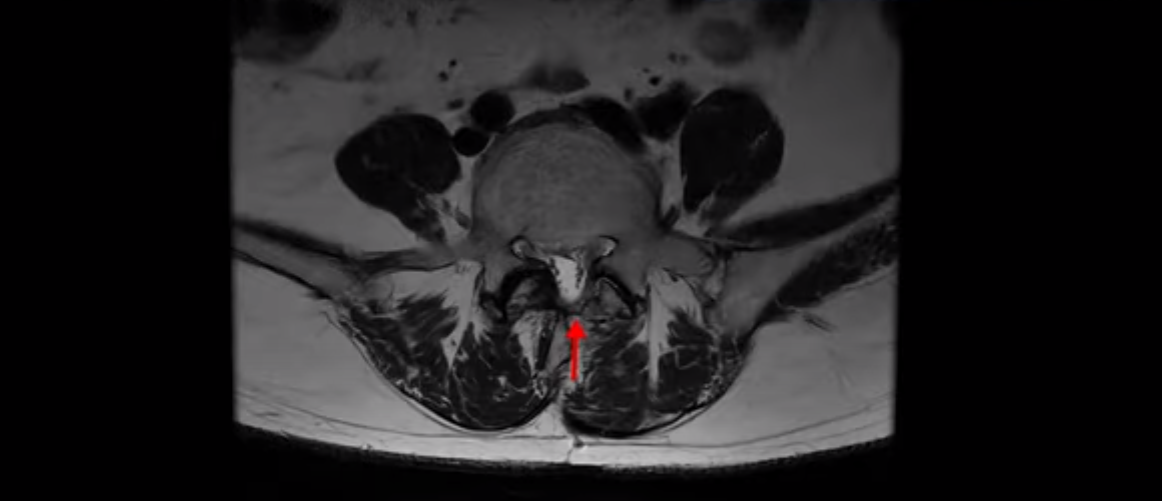

4번 5번에는 왼쪽으로 이전에 수술한 자국이 보이는데

수술한 부위에 상처 조직이 생겨 유착된 부위가 보입니다. 왼쪽, 오른쪽 신경 가지가 빠져나가는 추간공을 보면 오른쪽도 여러 마디가 좁아져 있고

왼쪽도 여러 마디가 좁아져 있습니다.

이렇게 허리 여러 마디와 신경 나가는 구멍 오른쪽, 왼쪽이 다 안 좋으니까 양쪽 엉덩이와 다리가 다 아픈 겁니다.